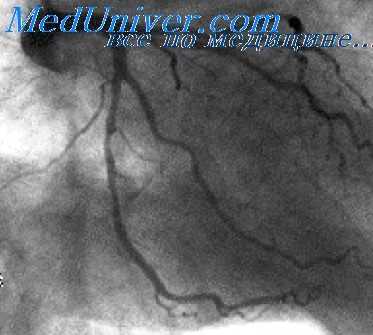

Рестеноз и стенты, элюирующие лекарственные средства, после ОИМ и при нестабильной стенокардии. Хирургическая операция на коронарных артериях возможна непосредственно после ОИМ, а также при нестабильной стенокардии. Стенты представляют собой искусственные кровеносные сосуды, используемые для замены пораженных атеросклерозом артерий, особенно коронарных, которые невозможно восстановить другими способами. Стенты, элюирующие лекарственные средства, высвобождают препараты из своего матрикса. Стент обеспечивает высокую концентрацию местно высвобождаемого препарата.

Такой способ доставки лекарственного средства можно использовать для эффективных средств, но способных вызывать серьезные побочные эффекты при их распределении по организму после системного введения. В настоящее время существуют многочисленные разнообразные стенты, элюирующие лекарственные средства, которые оказывают антитромботическое, антипролиферативное и противовоспалительное действие: сиролимус, такролимус, эверолимус, АВТ-578, биолимус, паклитаксел, QP2, дексаметазон, 17/3-эстрадиол, батимастат, актиномицин D, метотрексат, ангиопептин, ингибиторы тирозинкиназ, винкристин, митомицин, циклоспорин и антисмысловые препараты С-тус (Resten-NG, AVI-4126). Только для трех из этих лекарственных средств их эффективность доказана в рандомизированных исследованиях — паклитаксела, сиролимуса и эверолимуса. Существенный эффект при конечной ангиографической оценке не обязательно равноценен существенному клиническому эффекту.

Безопасность и эффективность ЧKB в незащищенных левых главных коронарных артериях все еще являются спорными. В США применение стентов, элюирующих лекарственные средства, остается предметом исследований.